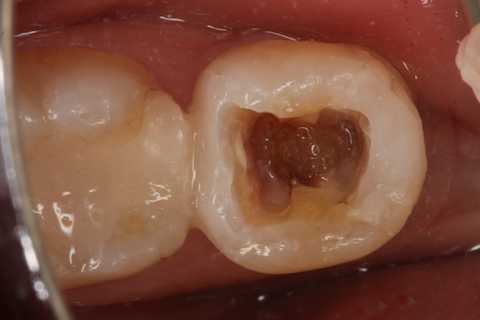

30代女性、左下7、Per、動揺度2.5

今日の症例は8年前に僕が親知らずが遠心に食い込んで虫歯になったものを神経を取らずにCR充填したものだが、とうとう接着剥がれが起こり神経が死んでしまった。神経は全く残っておらず。溶けてなくなっていた。

レントゲン写真では炎症は歯根周囲の歯槽骨に及んでいる。

この症例は歯根内部をいじられていないので、根管治療は難しくない。CRで歯冠を再建するのが難しかった。

再建が終わった後で、内部の治療をしてCRで埋め戻している。